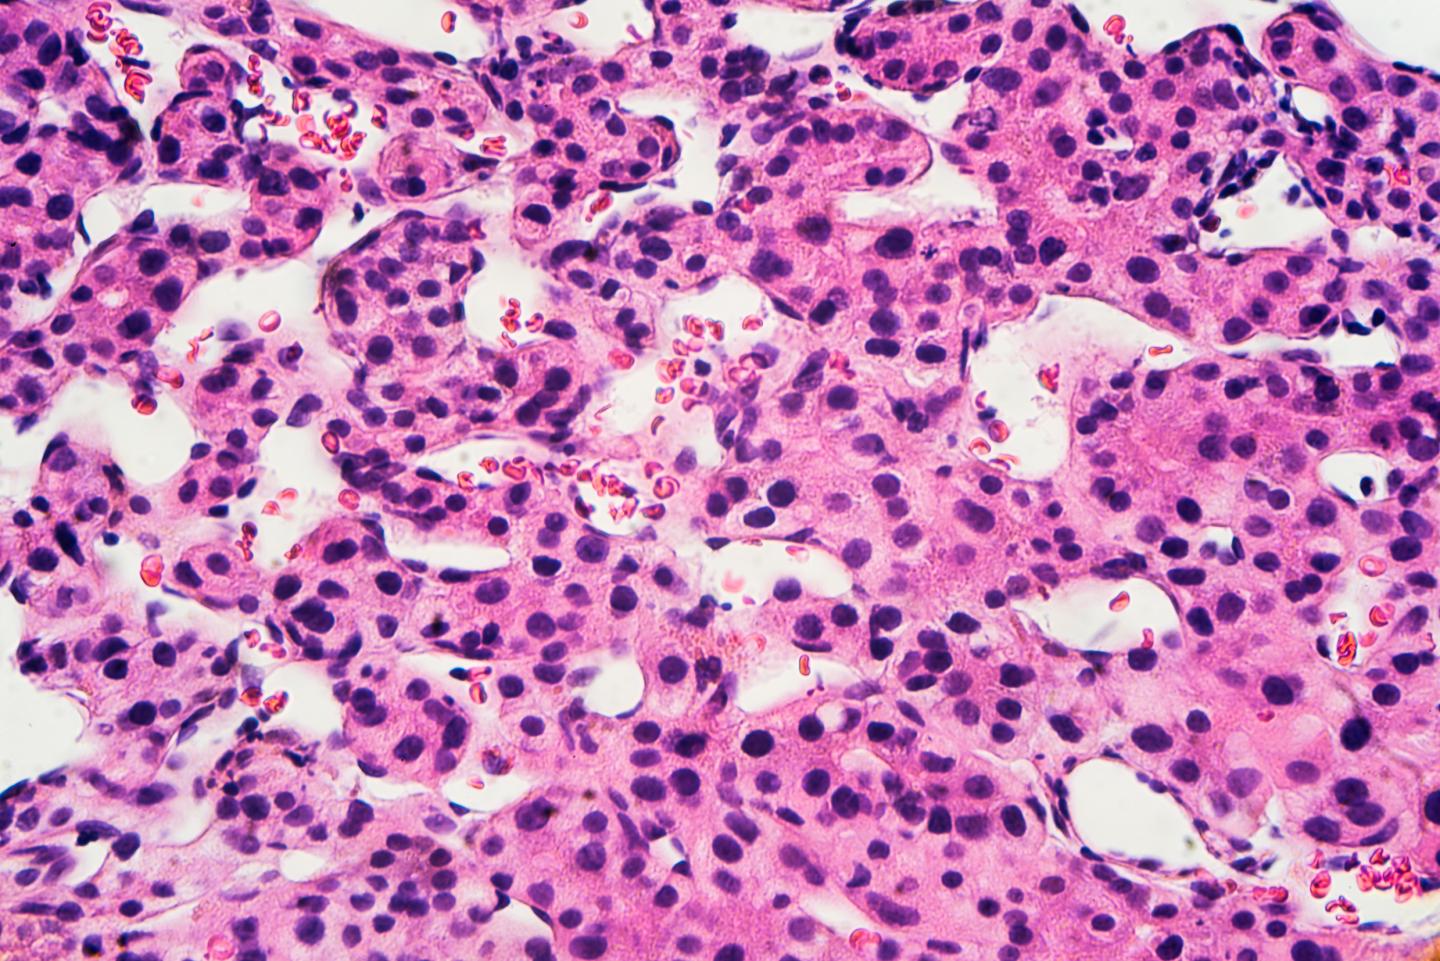

image: Microscopic image of hepatocellular carcinoma

There are five types of hepatitis viruses, with very different manifestations and consequences. Hepatitis A and E cause acute infections that can be severe but transient. Hepatitis B, C and D, however, can become chronic and cause liver dysfunction months or even years after infection. Although Hepatitis C is now well treated, Hepatitis B and especially D are still difficult to control. "The most serious consequence of Hepatitis B and D is hepatocellular carcinoma, explains Francesco Negro, Professor at the Department of Pathology and Immunology of UNIGE Faculty of Medicine and Head of the HUG Viropathology Unit. It was already known that co-infection of Hepatitis B and D accelerates the progression of cirrhosis. However, to what extent co-infection of Hepatitis B and D accelerates the progression towards this particularly aggressive liver cancer? This remained to be evaluated."